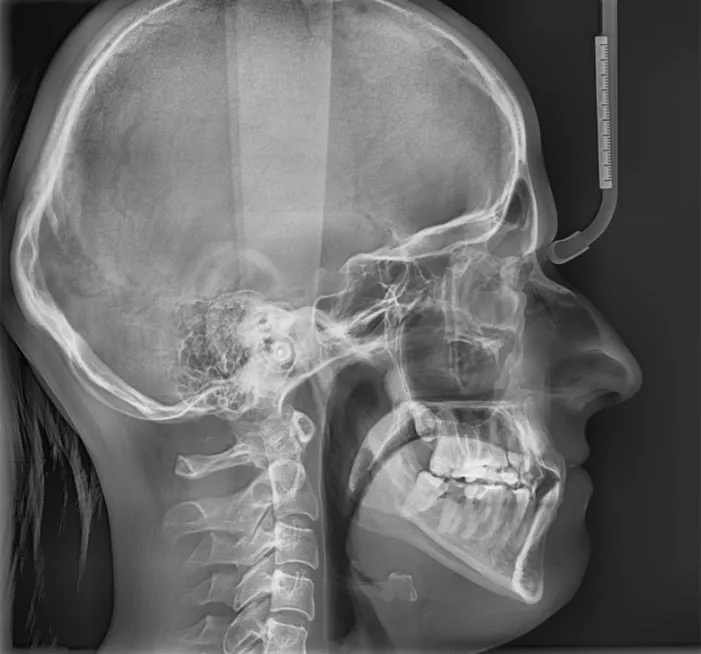

Zdjęcia RTG i wyciski: dlaczego precyzyjna diagnostyka jest fundamentem sukcesu?

Bez precyzyjnej diagnostyki, nie ma mowy o skutecznym planie leczenia. Dlatego przed założeniem aparatu zawsze wykonujemy szereg badań. Niezbędne są zdjęcia RTG pantomograficzne (przeglądowe zdjęcie wszystkich zębów) oraz często cefalometryczne (zdjęcie boczne czaszki, pozwalające ocenić relacje kostne). Dodatkowo pobieramy wyciski lub wykonujemy skany cyfrowe Twoich zębów, co pozwala na stworzenie trójwymiarowego modelu szczęk. Te wszystkie dane są fundamentem, na którym buduję indywidualny i precyzyjny plan leczenia, dopasowany do Twoich potrzeb.